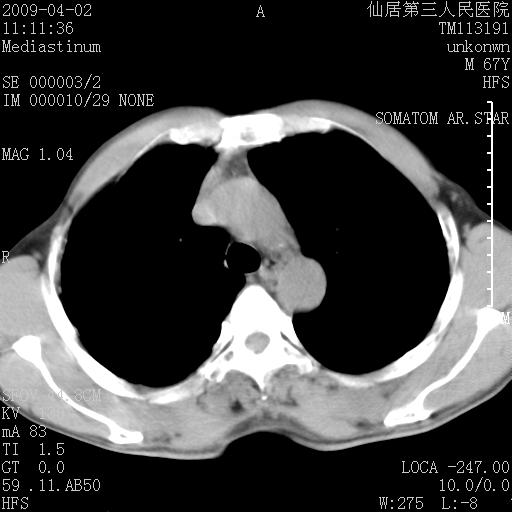

患者老年男性,乏力畏寒来诊,摄胸片示右下肺感染性病变,抗炎两周后复查胸片,无好转有进展。

后做ct平扫表现如下:

病灶呈蜂窝征,纵隔多个淋巴结肿大;肺泡癌需考虑

右肺下叶背段干酪性肺炎。请痰检[emb28]

考虑双肺间质性改变(间质纤维化?)伴右肺下叶感染。

支持11楼,考虑肺结核.年䶨;大,抗炎无效.纵隔淋巴结肿大.老年人下肺结核要警提